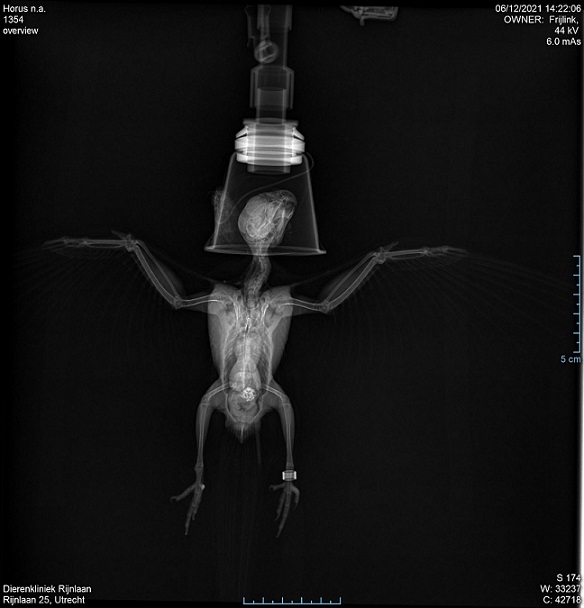

Röntgenfoto Horus

Zo had ik Horus nog nooit gezien. Ik staarde naar de rare zwartwit foto, gemaakt door een machine die door de huid heen kijkt en de ingewanden en botten blootlegt. Horus, een van mijn twee valkparkieten, werd een maand geleden plotseling ziek. Ach en oei, wat een verdriet en zorgen om mijn kleine grote held. Slapeloze nachten. In de 15 jaar dat deze vogels ons huishouden delen, zijn ze nooit ziek geweest. Valkparkieten kunnen wel 23 a 25 jaar worden. Mits ze gezond blijven. Omdat Horus ondanks zijn ziekte zoveel vechtlust toonde, fluisterde ik in zijn oortje: 'geen stad is te ver voor een knokker als jij'. Via lokale dierenartsen werd ik doorverwezen naar een specialist in Utrecht. Daar is deze röntgenfoto gemaakt.

Nee, zo had ik Horus nooit gezien. Röntgenfoto's zijn altijd raar, ze laten de vergankelijke binnenkant zien van dat vervoermiddel waarin onze geest onderdak heeft. Het is zo'n vreemd idee dat als die machine ermee ophoudt, wij ook ophouden. Het zien van de foto van Horus ontroerde mij; dat kwestbare en weerloze lijfje waarin dat eigenaardige zieltje woont met die enorme wilskracht.